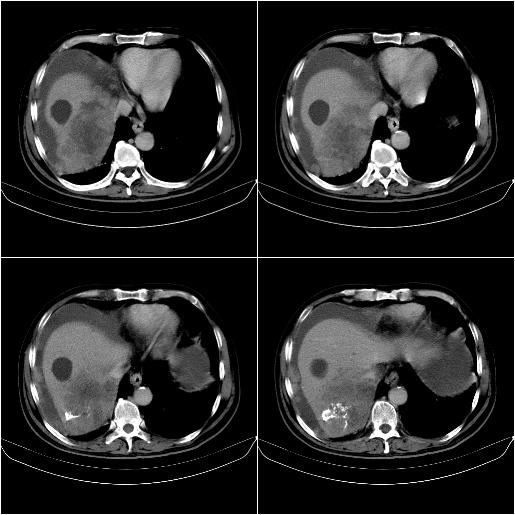

标题: CT21651:M,67Y,肝癌9月,介入术后3月。

m,67y,肝癌9月,介入术后3月。现腹胀、纳差、腹泻。

1)肝癌介入治疗术后碘油沉积不良。2)门静脉瘤栓形成,腹膜广泛性转移。3)肝硬化,脾大,腹水。4)慢性胆囊炎。